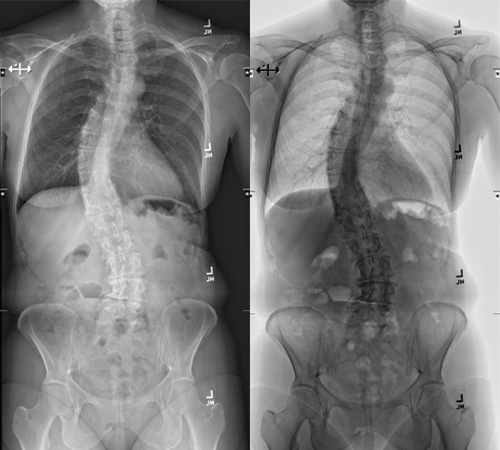

Spinal deformities, such as scoliosis and kyphosis, occur when the spine's curve isn't standard. An abnormally-curved spine can cause mild to severe symptoms ranging from stiffness to the inability to walk.

Scoliosis is one of the more common spinal deformities. While no cure exists, a curved spine can be treated and managed so patients can live an active, healthy life. Our doctors and therapists often help patients achieve their goals and restore confidence in their appearance.

Our scoliosis doctors at Och Spine perform routine and complex spinal deformity surgeries for children and adults. In addition to more common deformities, Och Spine scoliosis doctors are known worldwide for treating some of the most challenging cases. Through our specialized care, we help patients recover and go on to lead active lives.

We use the latest navigation technology and augmented virtual imaging for patients requiring surgery. Utilizing low radiation EOS scans and 3D CT scans, we can produce detailed spine pictures so the surgeon and the patient can see the anatomy. These advanced technologies allow us to perform precise and safe surgeries.